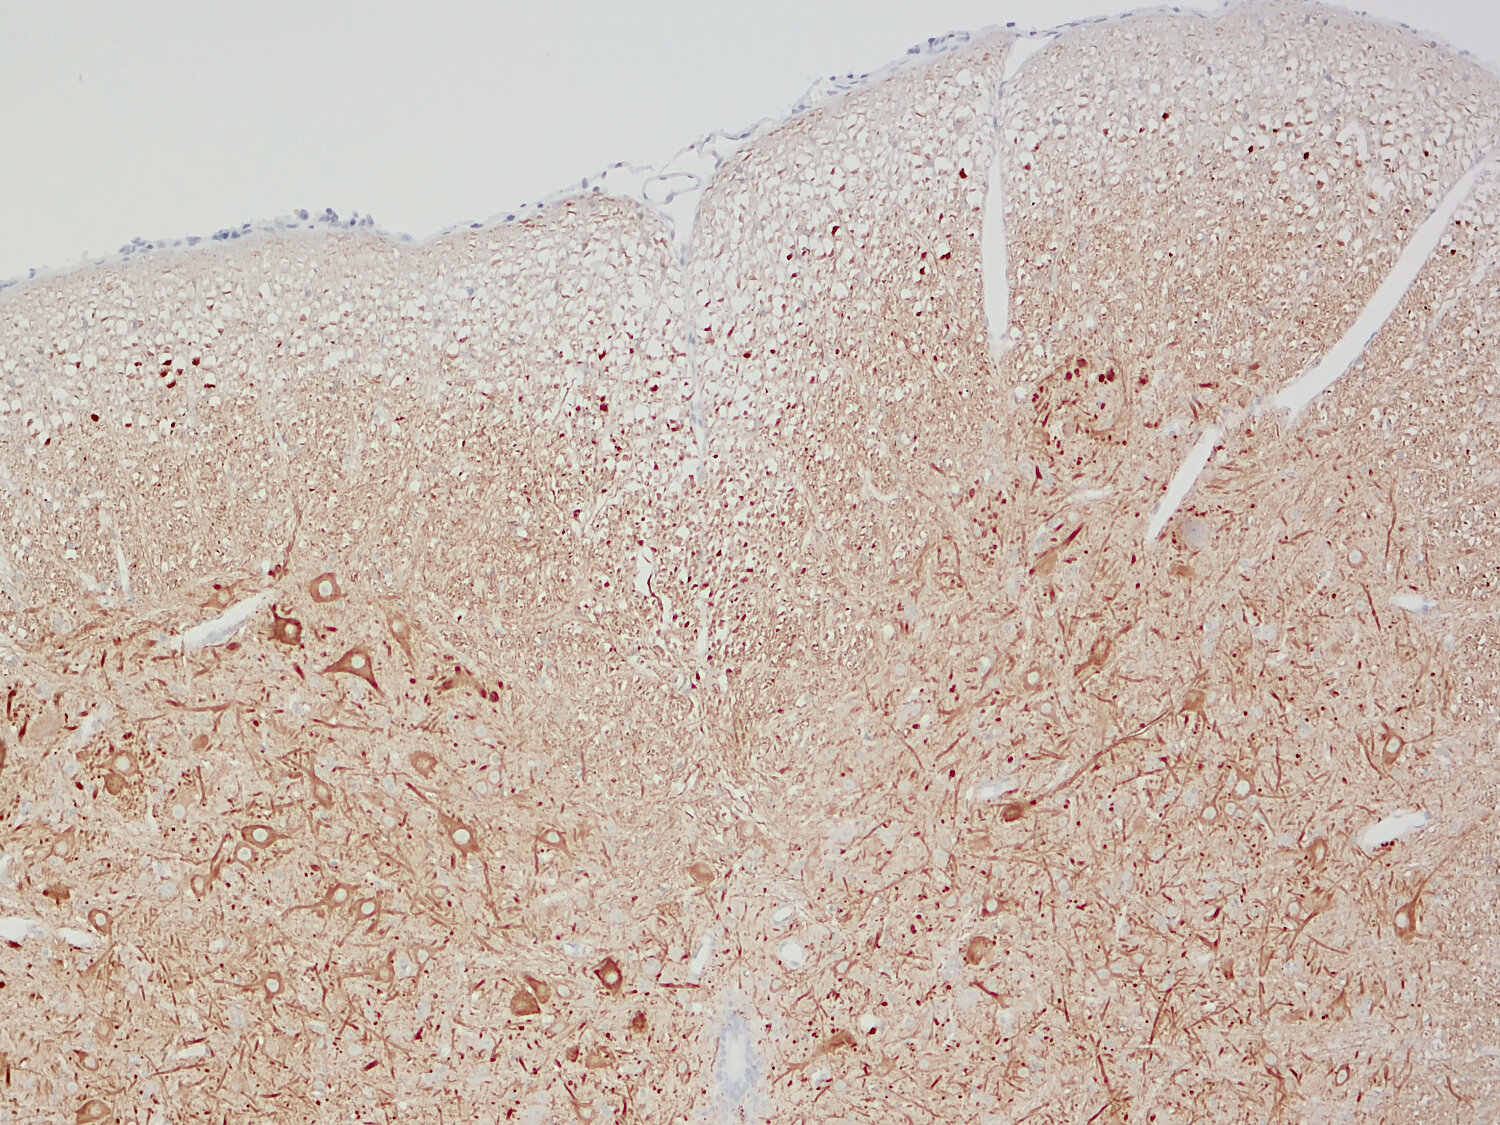

IHC: 1 : 500 gallery

IHC-P: 1 : 100 up to 1 : 1000 gallery

Immunohistochemistry (IHC) on 4% PFA perfusion fixed tissue with 24h PFA post fixation. Immunoreactivity is usually revealed by fluorescence or a chromogenic substrate. Some antibodies require special fixation methods or antigen retrieval steps. For details, please refer to the ”Remarks” section.

Immunohistochemistry (IHC-P) of formalin fixed, paraffin embedded (FFPE) tissue (some antibodies require special antigen retrieval steps, please refer to the ”Remarks” section). Immunoreactivity is usually revealed by fluorescence or a chromogenic substrate.

Beyond their structural function, neurofilaments are also valuable biomarkers in both research and clinical settings. They are widely used in immunohistochemistry to stain and visualize axons, particularly in peripheral nerves and the CNS. Increased levels of neurofilament proteins in cerebrospinal fluid (CSF) or blood are strongly associated with neurodegenerative diseases, such as amyotrophic lateral sclerosis (ALS), multiple sclerosis (MS), and Alzheimer’s disease (3). In peripheral nerve studies, neurofilament staining is often combined with other markers, such as S100, to provide a more comprehensive assessment of nerve structure and pathology (4).